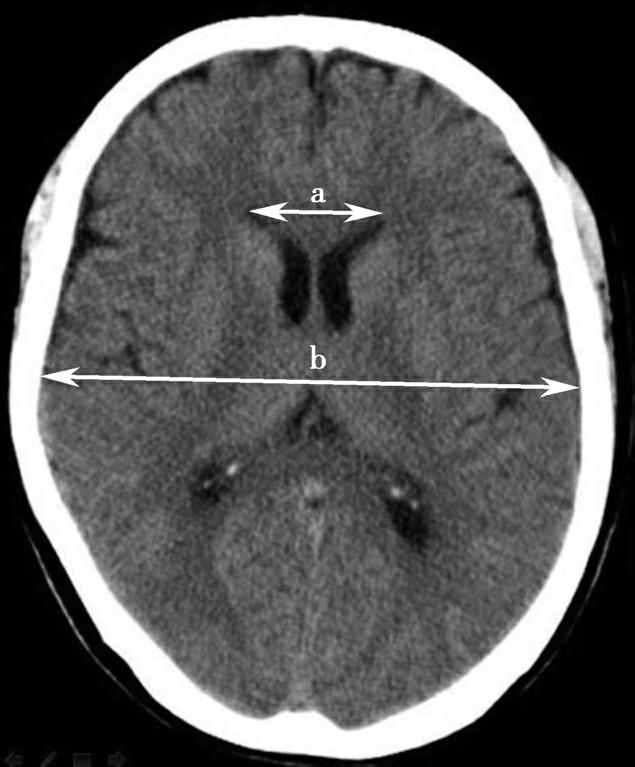

第三脑室正常成人前后径约12mm,左右宽约5mm,上下径也约为12mm。侧脑室后角两侧有时大小不等,右侧后角上下径约为38mm,左右径约为20mm;左侧后角上下径约为28mm,左右径约为15mm。测量双侧侧脑室前角间径与同平面脑横径的比值(R),正常平均值为30%。轻度扩大时为31%~39%,中度扩大为40%~46%,重度扩大时>47%。脑积水或脑萎缩等病理情况下脑室系统会扩大。不同年龄组正常脑室系统测量值存在差异,整体表现出测量值随着年龄增大而增大的趋势(图1-2-83、图1-2-84)。

图1-2-83 第三脑室测量

a线.第三脑室前后径;b线.第三脑室宽径

图1-2-84 侧脑室测量

R=双侧侧脑室前角间径(a)/同平面脑横径(b)